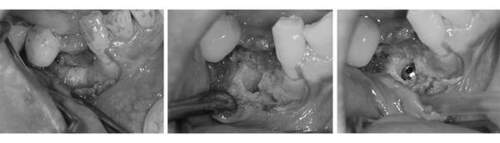

そのため、骨をてっぺんと穴の空いた部分に作る。 そのために、人工の骨をおき、チタンのメッシュで固定する。 この状態で6ヶ月ほど待機する。

麻布十番歯科のインプラント治療で人工の骨をおき、チタンのメッシュで固定している症例写真

6ヶ月後再び歯茎を切り中の状態を確認。骨がしっかりできており、インプラント手術を行えることが分かると思う。 インプラントを埋めるための穴をあけて、インプラントを埋入した。

麻布十番歯科のインプラント手術の症例

麻布十番歯科のインプラント手術の症例① 麻布十番歯科のインプラント手術の症例② 麻布十番歯科のインプラント手術の症例③